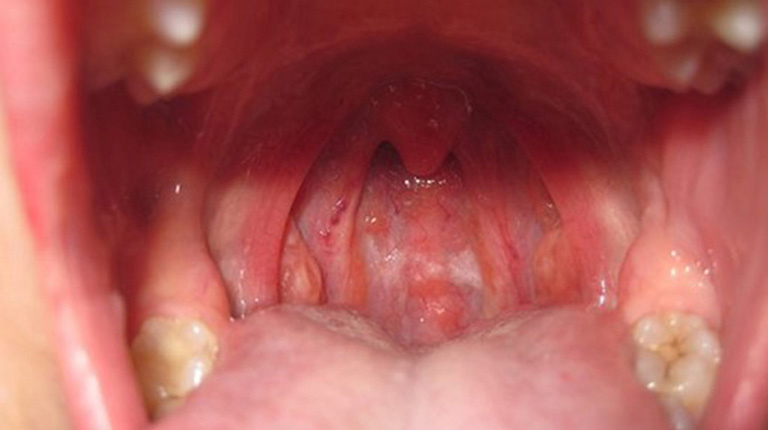

Viêm mũi họng là tình trạng niêm mạc mũi và họng bị viêm, phù nề, tăng tiết dịch, thường gặp ở trẻ em do hệ miễn dịch chưa hoàn thiện. Bệnh có thể xuất hiện đơn lẻ hoặc là biểu hiện khởi phát của nhiều bệnh lý hô hấp khác.

Trong viêm mũi họng, trẻ có thể gặp các triệu chứng như:

Sổ mũi (trong, đục hoặc xanh vàng)

Nghẹt mũi, thở bằng miệng

Ho khan hoặc ho có đờm

Đau rát họng, ngứa họng

Khàn tiếng nhẹ

Ăn uống kém hơn bình thường

Tuy nhiên, không phải mọi trường hợp viêm mũi họng đều kèm theo sốt, đặc biệt ở giai đoạn sớm hoặc khi mức độ viêm còn nhẹ.